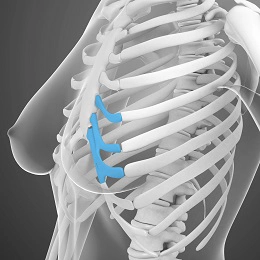

غضروف اتوژن چیست؟

غضروف گوش، غضروف تیغه بینی و غضروف دنده را غضروف اتوژن می گویند. و از آنجایی که غضروف اتوژن از بافت بدن شما است، بنابراین بعید است که پیوند غضروف در جراحی بینی باعث التهاب یا عوارض جانبی شود. در صورت عدم وجود غضروف به دلیل جراحی مجدد، غضروف دنده جایگزین غضروف خودزاد می شود.